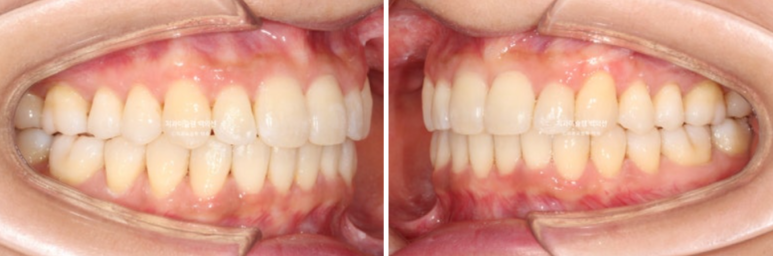

24.08~25.08

중심선, 과개교합, 덧니의 개선

옥니였던 앞니 각도가 정상각도를 찾았습니다.